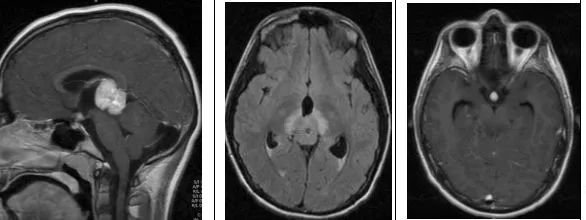

松果體母細(xì)胞瘤(WHO IV級(jí))

12歲兒童,矢狀位T1WI示松果體區(qū)低信號(hào)腫塊,橫斷位T2WI示一高信號(hào)腫塊右份伴局灶性低信號(hào),代表鈣化,注意與病灶相關(guān)的腦積水;橫斷位及矢狀位T1WI+C示明顯強(qiáng)化腫塊